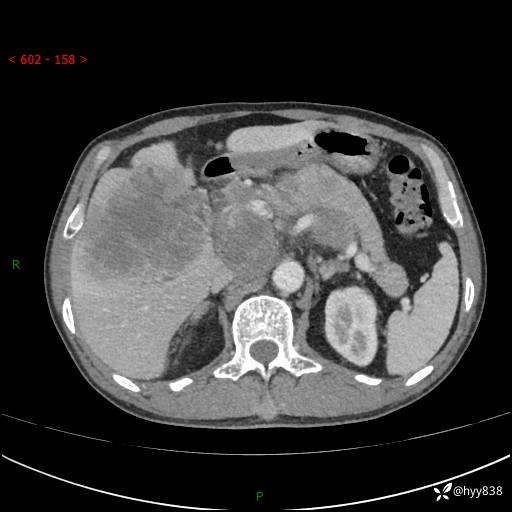

上腹部CT平扫+增强(两期)